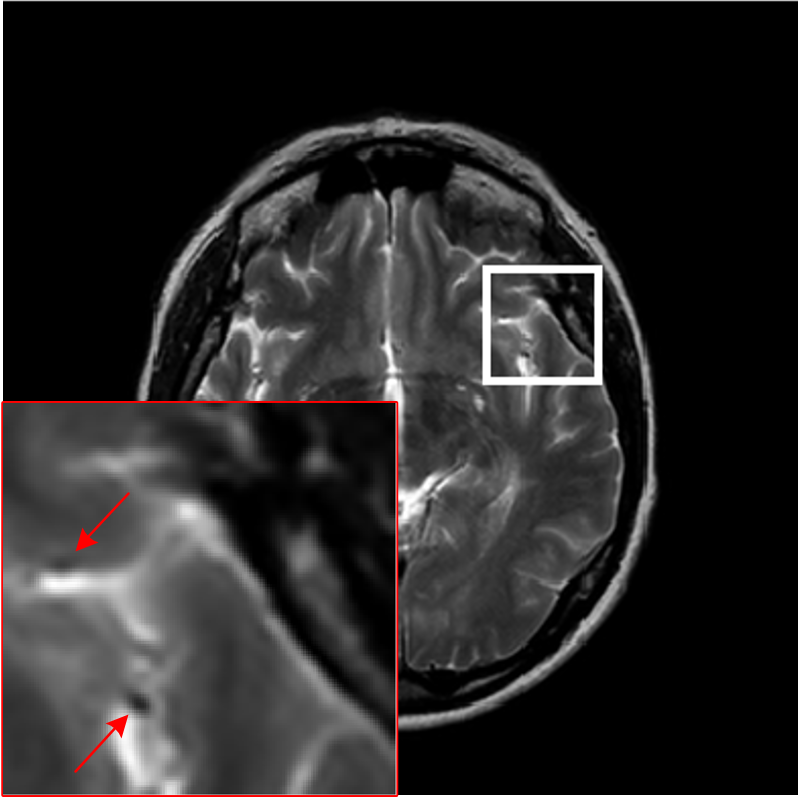

As shown in Figs. 7, 8 and 9, Sparse MRI and DLMRI have a lot of unpleasant artifacts, Residual learning and U-net can eliminate most of artifacts, but are not ideal for restoring image details. However, the proposed method can reconstruct better MR images, which outperforms other competitive methods in visualization of structures reconstruction and artifacts removal. Meanwhile, we can see from the absolute error residuals for three sampling experiments that the proposed MDN algorithm restores a finer detail structure than other algorithms. Moreover, we present the PSNR and SSIM values in Table I for different algorithms, sampling masks and sampling rates. It is demonstrated that the proposed method provides better reconstruction performance and visual results than other competitive methods. We can also see the obvious improvement of all algorithms over zero-filling both in visualization. In particular, a higher SSIM value of Sparse MRI appears when using 30% variable density random sampling, however, Sparse MRI generates more artifacts than the proposed MDN.

We evaluate the performance of the proposed model using PSNR on complex-valued data and compare with two optimization-based methods and three deep-learning methods. We present the PSNR results for all sampling masks and five rates in Figs. 10(a)-(c) and it is obvious that the proposed model outperforms other five methods, which can demonstrate the effectiveness of MDN model on complex-valued data. Additionally, we provide the standard deviation on 80 test images of different methods when using 30% sampling rates of three masks in Fig. 10(d). We can observe that deep-learning methods obtain more stable performance than DLMRI and Sparse MRI. In Figs. 10(e)-(j), we show the absolute value of residuals of different algorithms using 30% radial sampling rate. We can see that the proposed model has less noise-like errors than other five methods.